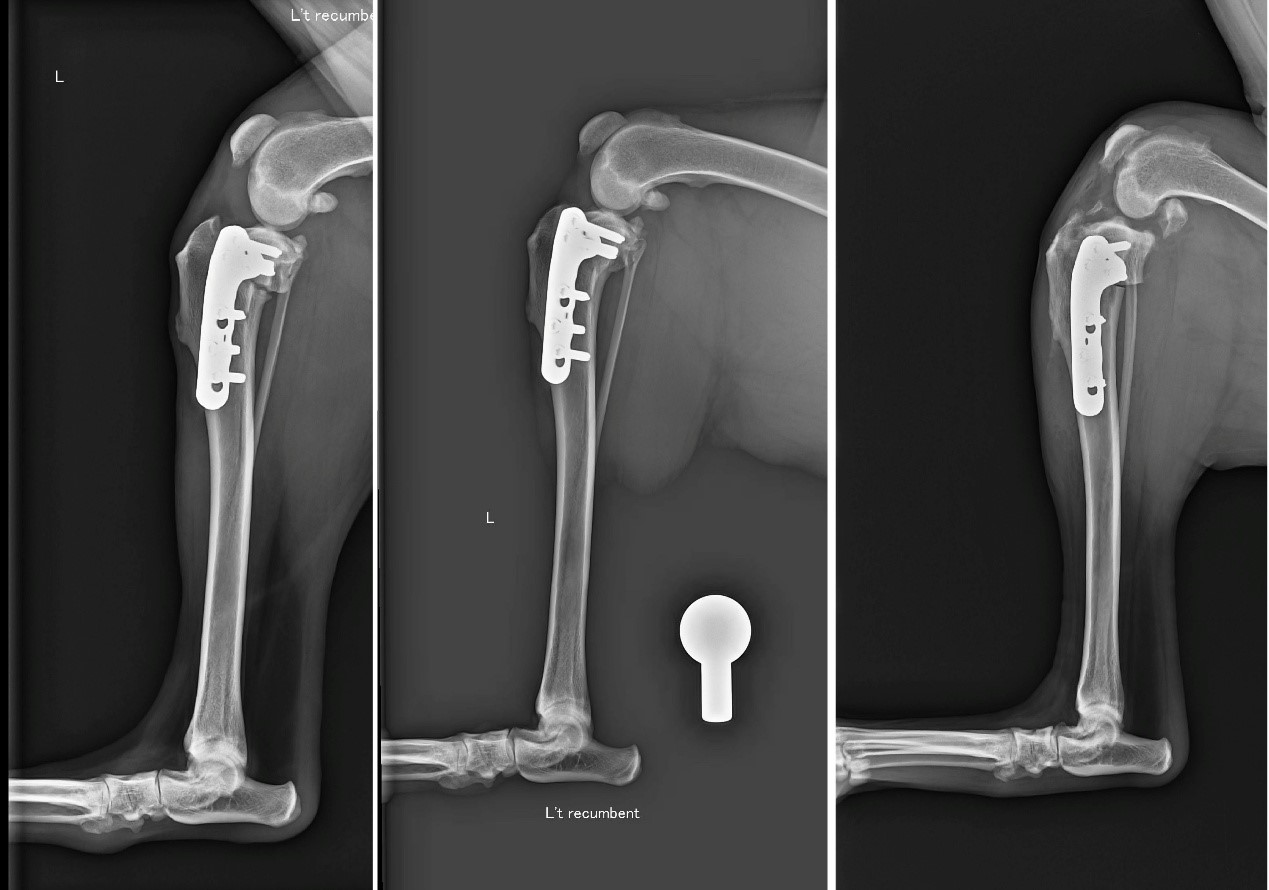

TPLO (Tibial Plateau Leveling Osteotomy) 是目前國際公認治療前十字韌帶斷裂的黃金標準手術。

它的原理非常巧妙: 既然韌帶斷了,我們不再執著於修補那條脆弱的韌帶,而是透過幾何力學的改變,將脛骨切開並旋轉角度,改變膝關節受力的平臺。術後,狗狗的膝蓋不再需要依靠前十字韌帶就能在行走時保持穩定。

一張含有 X 光影像, 醫學影像, 醫療, 放射學 的圖片AI 產生的內容可能不正確。